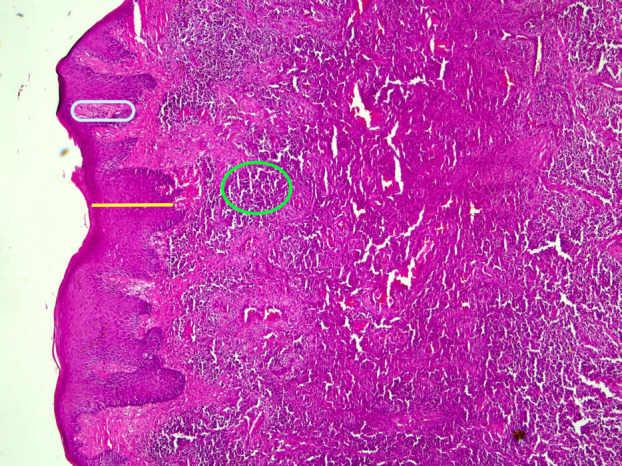

Congenital plasminogen (PLG) deficiency is an exceptionally uncommon hereditary disease associated with biallelic pathogenic / likely pathogenic variants in the PLG gene. Ligneous periodontitis (LP) is a rare disorder that can occur as a result of a lack of plasminogen. It is defined by the presence of lobulated, membranous, and ulcerated masses in the gums, as well as significant damage to the surrounding bone. This case report presents the diagnosis, treatment, and follow-up outcomes of a 23-year-old male patient who referred to our clinic with a complaint of widespread gingival enlargement. We identified a novel c.2087G>C (p.Arg696Pro) variant with a known variant detected in a compound heterozygous state in PLG confirming the molecular etiology. This case report emphasizes the importance of dentists identifying oral manifestations of various systemic diseases. Careful examination of such findings and the timely referral of patients to appropriate specialists for diagnosis and treatment are of critical significance. Key words:Ligneous periodontitis, plasminogen deficiency, genetic confirmation, histopathological diagnosis.